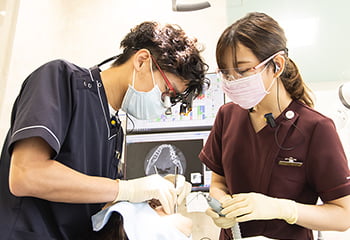

マイクロスコープ

マイクロスコープ(歯科用顕微鏡)を用いることで、視野を肉眼の数十倍に拡大して患部を観察することができます。目に見えない小さな虫歯や、歯の細かなひび割れ、歯の神経を抜いた後にできる根管内も、明るく照らしながら拡大して、視覚的根拠のある治療が行えます。

例えば、マイクロスコープを使って虫歯を丁寧に削ることで、天然歯と詰め物・被せ物の間に隙間を作らないようにすることが可能です。隙間から細菌が入り込むと、詰め物などの下で虫歯が再発する可能性があります。虫歯を始め、歯周病治療、型取り、インプラント治療など、様々な分野においてマイクロスコープによる精密治療は役立ちます。